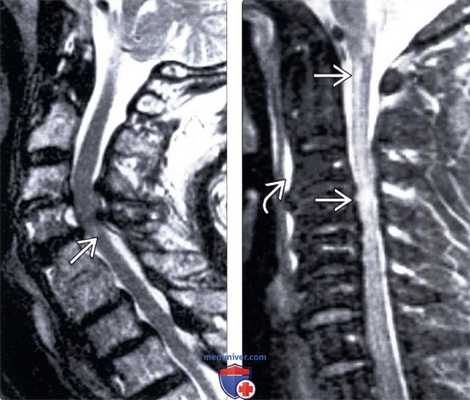

(Слева) На Т2 МР-миелограмме отмечается фокальная деформация и изгиб грудного отдела спинного мозга. Обратите внимание на смещение края дурального мешка, свидетельствующее об экстрадуральном накоплении контраста, связанном с наличием дефекта твердой мозговой оболочки.

(Справа) На Т2 CISS МР-И определяется пролаби-рование спинного мозга через дефект твердой мозговой оболочки, а также экстрадуральное скопление жидкости вдоль вентральной поверхности дурального мешка. Обратите внимание на наличие также грыжи межпозвонкового диска.